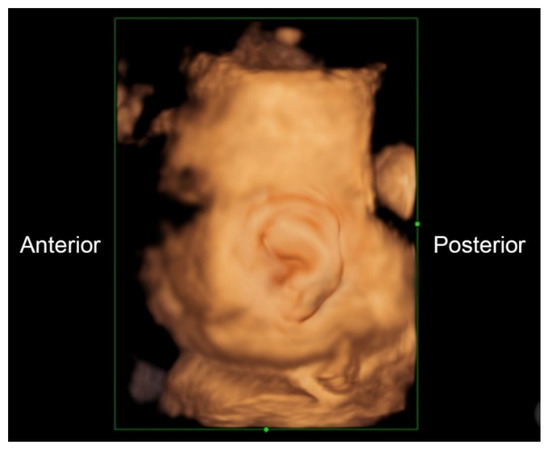

A 32-year-old pregnant woman, G4 P2102, attended her first visit of antenatal care at 23+3 weeks of gestation. Ultrasound examination for anomaly screening demonstrated cardiac defects, including double-outlet right ventricle: DORV-TOF type, with severe pulmonary stenosis (Figure 1) and left superior vena cava. Detailed ultrasound showed no associated abnormalities. Fetal biometry was consistent with gestational age except abdominal circumference and estimated fetal weight, which were relatively low (at 10th percentile), reflecting some degree of growth restriction. However, detailed ultrasound on the follow-up scans at 28 weeks of gestation showed subtle abnormalities, including malrotation of both kidneys, the hilum or renal pelvis facing posteriorly to the abdominal wall (Figure 2). Furthermore, 3D-ultrasound revealed abnormal external ear structure (markedly prominent crus of anti-helix) (Figure 3). Non-stress tests (NST) showed spontaneous fetal heart rate (FHR) accelerations (normal reactive tests) (23+3 weeks). Interestingly, the fetus showed persistent non-response to acoustic stimulation tests at 26, 30, 32, 36 and 38 weeks (no FHR accelerations as well as no quickening perceived by ultrasound) (Figure 4), probably reflective of auditory dysfunction. Based on the findings of heart defect, ear defect, renal defect and growth restriction, several differential diagnoses were listed, including CHARGE syndrome. Theoretically, fetal blood sampling for molecular genetic tests should be performed. Nevertheless, since no lethal condition was identified and the couple wanted to continue pregnancy regardless of investigation results, prenatal invasive diagnosis was avoided, and we waited for postnatal work-up instead. She had no significant underlying disease and no familial history of hereditary diseases. Her pregnancy was uneventful except that she developed gestational diabetes (GDM) at 28 weeks of gestation, which was well-controlled with diabetic diet.

Figure 1. Double-outlet right ventricle (DORV): (A) TOF type, small pulmonary artery (PA) and (B) reverse flow in the ductus arteriosis (DA) (Ao: ascending aorta; AoA: aortic arch; LV: left ventricle; RV: right ventricle; Sp: spine; VSD: ventricular septal defect).